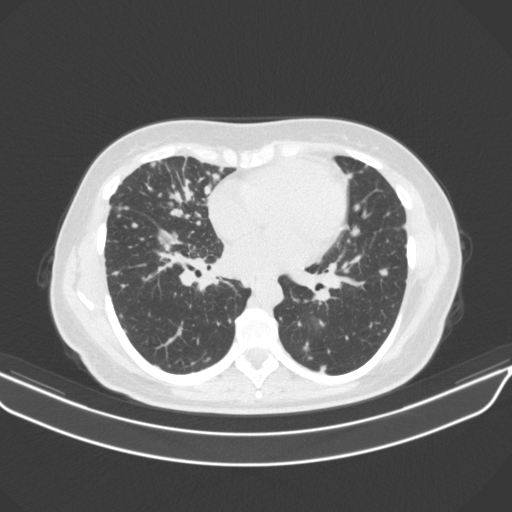

Generated VENOUS CT scan (A→B translation)

No window - Raw intensity values

Lung window (WL -600, WW 1500 β†’ Low βˆ’1350, High +150)

Mediastinum window (WL 40, WW 400 β†’ Low βˆ’160, High +240)

Targeted Slice 70 - Lung Window Analysis (Generated vs Real Venous)

0.752

Lung SSIM

110.9

Lung RMSE

46.5

Lung MAE

Targeted Slice 70 - Mediastinum Window Analysis (Generated vs Real Venous)

0.759

Mediastinum SSIM

45.2

Mediastinum RMSE

16.1

Mediastinum MAE